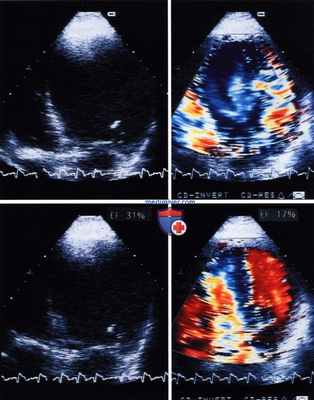

Фракция выброса левого желудочка (ФВ) у того же пациента с дилатационной кардиомиопатией, по данным радионуклидной вентрикулографии, составила 19%.

По данным двумерной эхокардиографии в четырехкамерной позиции (слева вверху окончание диастолы, слева внизу окончание систолы), при очевидном ограничении эхогенности, оценка ФВ составила 31%, а по данным допплера с контрастным усилением (справа) на фоне отчетливого улучшения отграничения эндокарда - 17%.